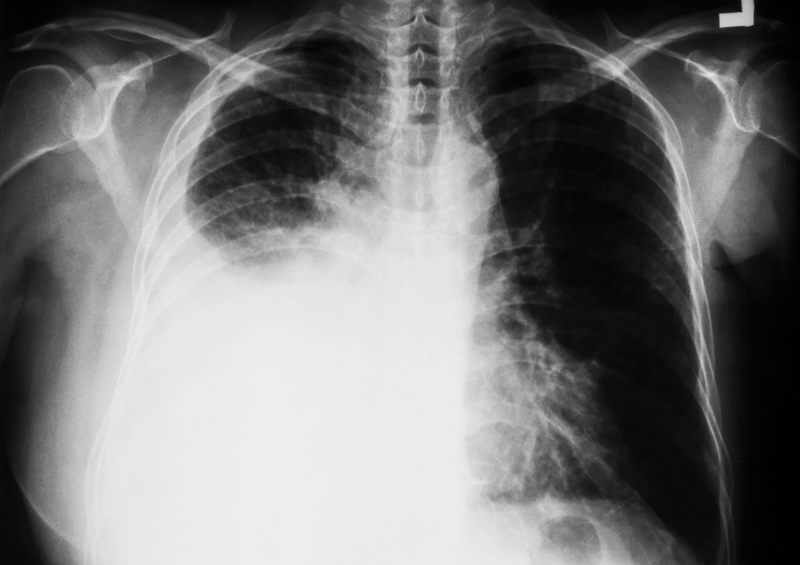

Tràn dịch màng phổi có tái phát không? Theo nghiên cứu tỉ lệ tái phát sau điều trị vẫn còn khá cao, ở một số cá thể khả năng tái phát bệnh rất nhanh chóng sau điều trị. Để tìm hiểu rõ hơn về vấn đề này, hãy cùng tìm hiểu qua bài viết dưới đây.

Để trả lời cho câu hỏi tràn dịch màng phổi có tái phát không thì câu trả lời là có. Ở một số bệnh nhân, bệnh có thể tái phát nhanh chóng. Tuy nhiên, tình trạng này không xảy ra ở tất cả các bệnh nhân bị tràng dịch màng phổi. Một nghiên cứu trên 288 bệnh nhân tràn dịch màng phổi cho thấy sau 6 tháng tỷ lệ không tái phát là 76,6% và sau 12 tháng là 73,3%.

Một nghiên cứu khác trên 988 bệnh nhân mắc bệnh cho thấy tỷ lệ tái phát lâu dài rất cao, với hơn 30% bệnh nhân bị tái phát vào ngày thứ 15. Tràn dịch màng phổi có tái phát không? Nếu không xác định được nguyên nhân và điều trị cũng như không có cách điều trị thích hợp thì bệnh sẽ tái phát. Kết quả là có thể xảy ra tràn dịch màng phổi nhiều lần, ảnh hưởng đến chức năng phổi và khả năng hô hấp của người bệnh bị ảnh hưởng nghiêm trọng.